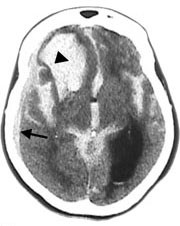

Subaraknoidalblødning ble påvist ved CT-undersøkelse hos 64 av 70 pasienter (91 %). Blod ble hyppigst påvist i basale cisterner (75 %), i fissura Sylvii (73 %) og i cerebrale kortikale sulci (67 %) (tab 1, fig 1 – 5). Funn forenlig med økt intrakranialt trykk (utvidet ventrikkelsystem, spesielt sideventriklenes temporalhorn og/eller overskyvning av midtlinjestrukturer, endret form av basale cisterner, utvisket overflaterelieff og/eller periventrikulært ødem) ble påvist hos 26 pasienter (41 %).

Opplysninger vedrørende cerebral angiografi forelå hos 64 av 70 pasienter med subaraknoidalblødning. Av disse hadde ti (16 %) normalt funn. Til sammen 63 aneurismer ble påvist hos 52 pasienter (81 %). Intracerebral arteriovenøs malformasjon ble påvist hos to pasienter. Hos seks pasienter ble det gjort samtidig funn av henholdsvis fire (n = 2), tre (n = 1) og to (n = 3) aneurismer ved samme undersøkelse. Aneurismer ble hyppigst påvist på a. cerebri media, a. communicans anterior og a. carotis interna (tab 2). Påvisning av blod i subaraknoidalrommet kunne gi indikasjon på lokalisering av aneurismet (tab 2, fig 2, fig 4). Prediksjon for påvisning av lokalisasjon av blødende aneurisme var kun meget god for aneurismer på a. cerebri media, hvor 12 av 13 aneurismer ble lokalisert korrekt. Det var dårligere prediksjon for aneurismer lokalisert til a. communicans anterior og a. carotis interna, med henholdsvis 11 av 18 og fire av ti aneurismer riktig lokalisert. Angiografi var utført hos åtte av ti pasienter med blod i septum pellucidum, og hos samtlige ble det påvist aneurisme på a. communicans anterior (fig 4). For de andre lokalisasjonene var det få observasjoner og lav treffsikkerhet.

I tillegg til å gi informasjon om blødning vil cerebral CT kunne påvise komplikasjoner til subaraknoidalblødning, som intracerebrale hematomer, akutt hydrocephalus, ødem eller iskemi. Funn forenlig med økt intrakranialt trykk ble påvist hos 41 % av pasientene i vår studie. Rinkel og medarbeidere (14) påviste hydrocephalus hos 11 av 40 pasienter med perimesencefal blødning uten aneurisme, og oppgav at blod i samtlige perimesencefale cisterner gav høy risiko for utvikling av hydrocephalus.

Cerebral CT vil ofte kunne gi informasjon om lokalisering av aneurismet som ligger til grunn for blødning (8). Tidligere studier har vist at treffsikkerheten for lokalisering av aneurisme ut fra CT-undersøkelse kun var høy ved ruptur av aneurismer lokalisert til a. communicans anterior og a. cerebri anterior (15, 16). I vår studie fant vi høyest treffsikkerhet når det gjaldt blødning fra aneurisme på a. cerebri media, også med riktig sideangivelse, mens treffsikkerheten med hensyn til blødning fra aneurisme på a. communicans anterior var dårligere. Septum pellucidum-hematom er ansett som et sikkert tegn på aneurisme på a. communicans anterior (8), og dette ble bekreftet i vår studie. Derimot vil ikke alle aneurismer lokalisert til a. communicans anterior blø til septum pellucidum. Enkelte angir at blod i fissura interhemisphærica er et sikkert og hyppig tegn ved aneurismer på a. pericallosa, men dette var ukjent for oss da bildene ble gjennomgått. Lokalisering av blødende aneurisme før radiologisk eller kirurgisk sikring er spesielt viktig når det foreligger flere aneurismer. Multiple aneurismer, vanligvis to eller tre, kan finnes hos 20 – 30 % av pasienter med intrakraniale aneurismer (17). I akutte situasjoner kan det hende at pasientens tilstand ikke tillater den tidsbruk som går med til angiografi. En ”nødoperasjon” er helt avhengig av at CT viser og kan tolkes med størst mulig sikkerhet med hensyn til lokalisasjon.